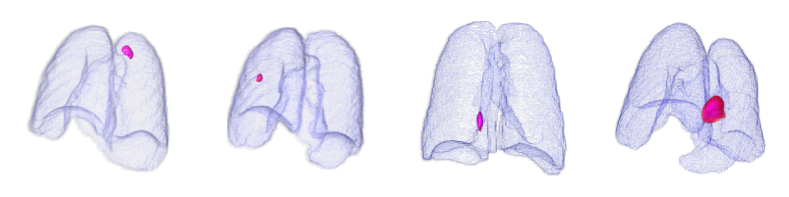

3.5 External validation using public lung cancer CT dataset

The experimental results presented thus far (Sections 3.4.1, 3.4.2, 3.4.3, and 3.4.4) show verification using SMC internal data (i.e., anomaly detection for pneumonia, tuberculosis, and both diseases). In this section, we further confirm the superiority of the proposed VMPR-UAD by demonstrating its high performance on external data, that is, the MSD dataset with 95 3D stacks showing lung cancer [35]). The anomaly detection results of VMPR-UAD are shown as ROC curves with AUC in Fig. K. VMPR-UAD provides high anomaly detection performance (at least 0.98) for different numbers of projections, with a higher diagnostic performance achieved when using more projections. As this trend is the same as that obtained from internal data, we can infer that VMPR-UAD consistently provides high diagnostic performance regardless of the CT dataset.

Finally, we evaluated the 3D abnormal (lesion) localization performance of the proposed VMPR-UAD. Of the 63 cancer cases in the MSD dataset with ground-truth annotations available, we excluded two cases (cases 38 and 96) of incorrect annotation or showing other diseases. We calculated whether the cancer area predicted by VMPR-UAD (binarized at a certain high-probability threshold) overlapped with the annotated cancer area. As a result, 57 of the 61 cases showed overlapping, demonstrating that VMPR-UAD can localize 3D lung anomalies (cancer in this case) with an accuracy of 93. Some localization examples in 3D data are shown in Fig. L. The red points in Fig. L(b) show the 3D cancer locations that the proposed method estimates with the highest confidence (i.e., location of highest pixel value in the 3D anomaly map). The red points in Fig. L(a) show the ground-truth cancer location. The ground truth and prediction shown in Fig. L confirm that VMPR-UAD correctly finds the lung anomaly 3D region. More detailed visualization results are available in the Supplementary Material. The prediction consistency can also be observed in 2D slices, as shown in Fig. M, where our anomaly localization map indicates correct cancer regions. Hence, the proposed VMPR-UAD can automatically localize or segment lesions without requiring any lesion information (i.e., using only CT slices from healthy subjects) for training.